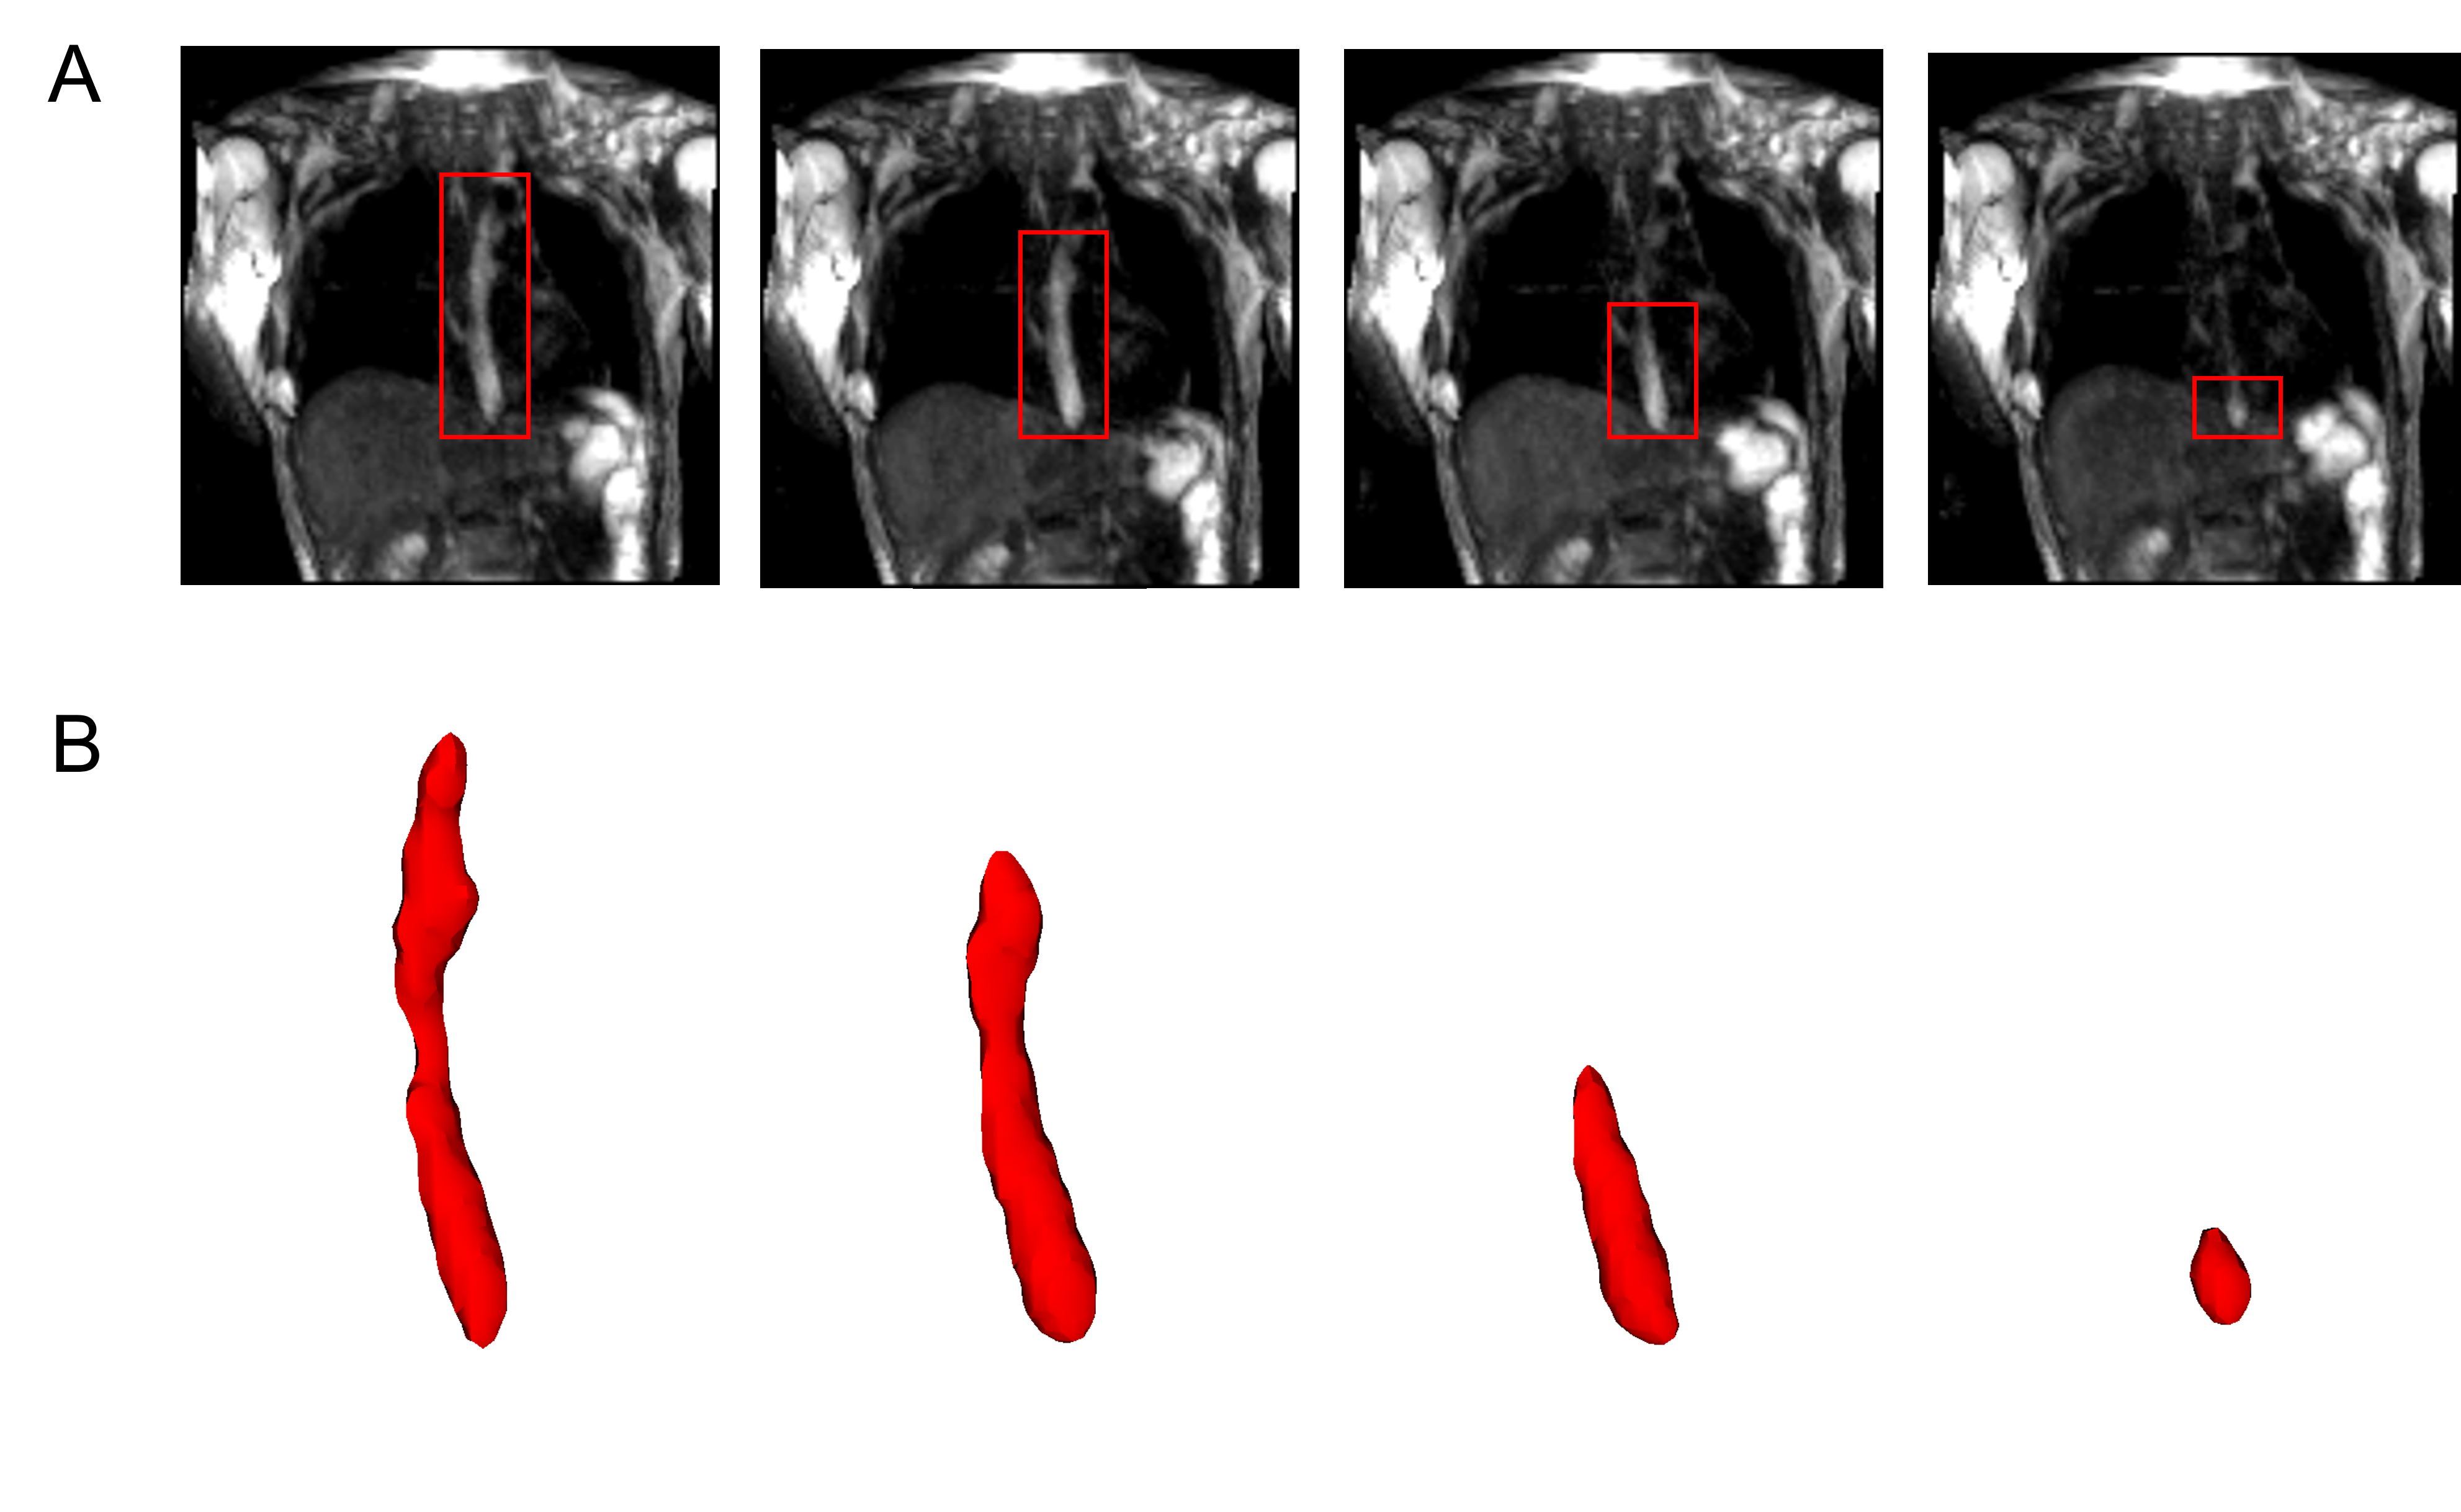

The MRI output consisted of a cuboid wherein voxels in a Cartesian coordinate system had different magnitudes of intensity. The temporal resolution of the dynamic MRI (1.17 second) determined the number of images with the bolus seen within the esophagus; 7 time instants in this study. The typical length of an adult esophagus is 18 - 25 cm [27]. The average velocity of a normal peristalsis is approximately 3.3 cm/s [28]. Thus, an average swallow sequence usually takes 5 - 8 seconds. Therefore, temporal resolutions similar to what we used in our analysis typically result in 5 - 8 images. Although this temporal resolution is not comparable to fluoroscopy, the detailed three-dimensional geometry of the bolus in MRI leads to better prediction of velocity and intrabolus pressure resulting in better prediction of esophageal wall properties. The bolus was manually segmented for the 7 time instants, a few of which are shown in Figure 2. The segmentation assigned a value of 1 and 0 to each voxel that lay inside and outside the bolus, respectively. The image segmentation was performed using the open-source software ITK-SNAP [29]. With improved MR imaging and better temporal resolution, manual image segmentation might not be feasible and more sophisticated automated segmentation techniques might be necessary. We have described a deep learning based automated segmentation approach called 3D-U-Net [30] in the Appendix which was fine-tuned for this application.